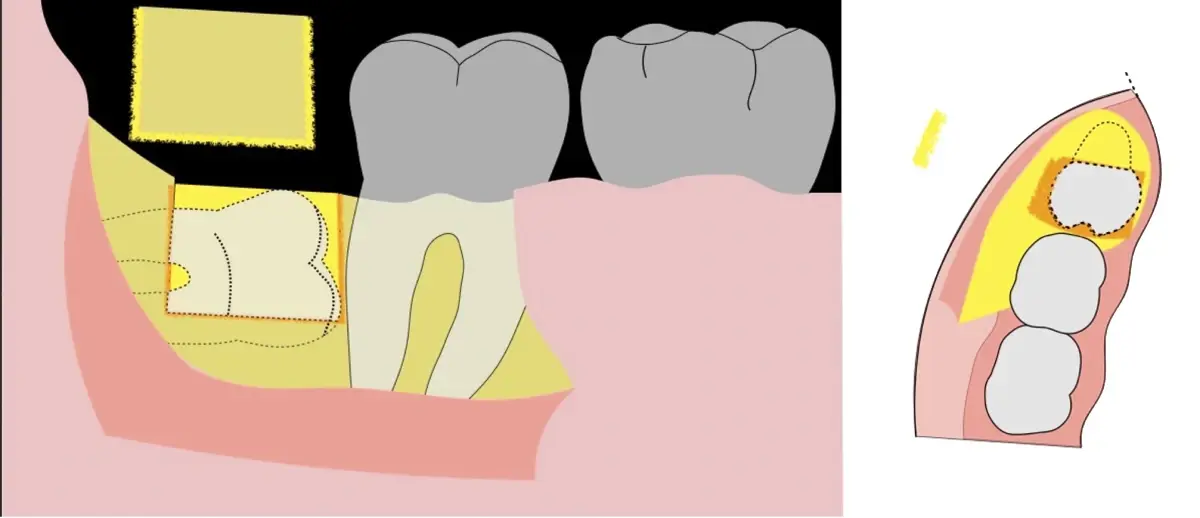

Es imprescindible conocer la ubicación de la tercera molar. Se puede emplear, adicionalmente a la evaluación clínica, herramientas radiográficas (panorámica y periapical) y tomográficas (Cone beam) para determinar la posición, grado de retención y proximidad a estructuras vecinas de riesgo como el nervio dentario inferior y así evitar lesiones (Figura 1).

El procedimiento se inicia colocando anestesia troncular para bloqueo del nervio dentario inferior y sus ramas. Luego, se establecerá el diseño de acceso según la disposición de la molar a extraer. Para fines didácticos, se explicará cómo se realizaría la extracción de la molar de la Figura 1: se realiza una incisión horizontal a nivel de la zona retromolar hasta llegar a distal de la segunda molar, continuándose con una incisión intrasurcular hasta mesial de la segunda molar, finalizando con una incisión vertical a espesor total hasta llegar a la línea mucogingival (Figura 2).